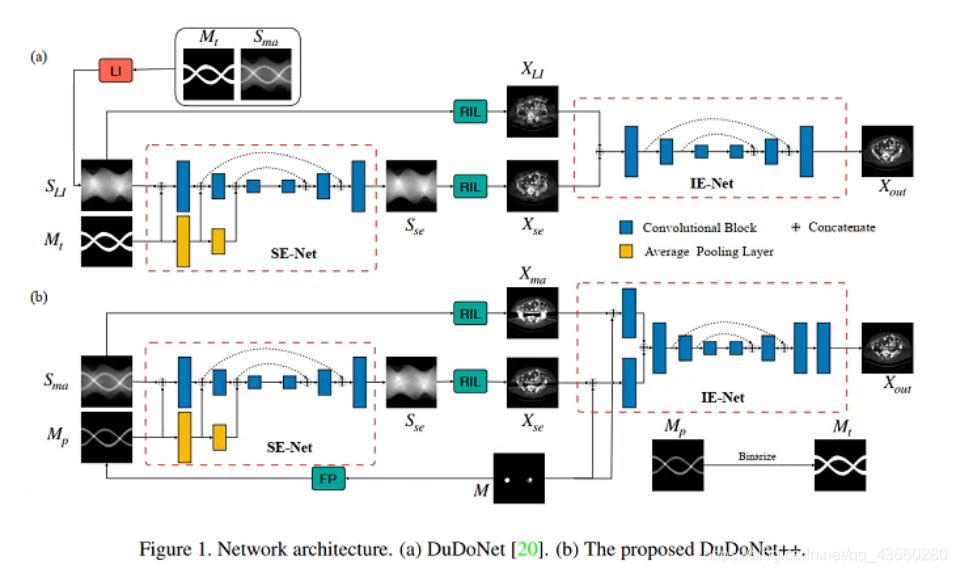

网络框架

该网络包括三个部分:

正弦图增强网络(SE-Net)、反演层(RIL)、图像增强网络(IE-Net)

- 正弦图增强网络(SE-Net):

输入是由金属伪影的正弦图Y和金属掩模投影二值化Mt线性插值的YLI和金属掩模投影二值化Mt组成,输出是增强的金属伪影的正弦图的Yout,掩模金字塔U-Net架构,保留了多尺度的金属掩模信息。 - 图像增强网络(IE-Net):

输入是由SE-Net的输出Yout反投影到图像域的X^和YLI反投影到图像域的XLI组成,输出是增强的金属伪影的图像域图像的Xout,IE-Net通过残差学习精炼CT图像。 - 反演层(RIL):

RIL使用滤波反投影(FBP)算法重建CT图像

网络结构

该网络也包括同样的三个部分:

正弦图增强网络(SE-Net)、反演层(RIL)、图像增强网络(IE-Net)

改进的点

- 正弦图增强网络(SE-Net)的输入:

1.由金属伪影的正弦图Sma和金属掩模投影二值化Mt线性插值的SLI改进成了直接利用带金属伪影的正弦图Sma,不用线性插值了。

2.金属掩模投影二值化Mt改进成了原始金属掩模的投影Mp - 图像增强网络(IE-Net)的输入:

1.由SLI反投影到图像域的XLI改进成了带金属伪影的图像域图像Xma

2.增加了原始金属掩模M concatenate输入

- 提出了Encoding Metal Mask Projection方法,直接利用带金属伪影的正弦图和图像,同时使用了原始金属掩模的投影

- 对于SE-Net,采用U-Net结构以原始的金属掩模投影为输入,并对其进行编码,以最大限度地利用掩模投影的知识。

- 对于IE- net,直接使用受金属影响的图像和原始金属掩模作为输入,而不是使用由线性插值正弦图重建的合成图像。

- 还引入了一种针对正弦图设计的填充方案sinogram padding,通过增加投影角度和射线的数量来避免采样不足的影响